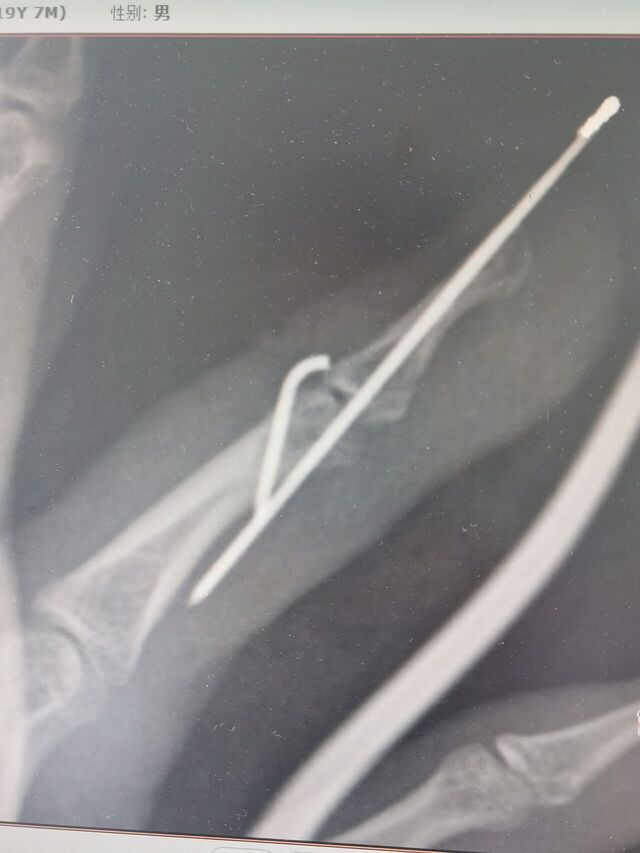

克氏针压扣法治疗骨性锤状指

昨天做了两例

效果都很好